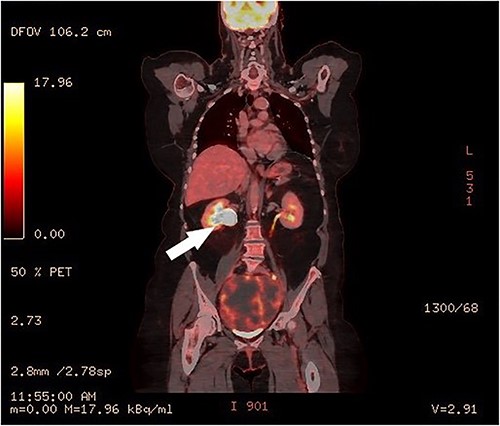

Clinical vaginal examination revealed a circumferentially distended uterine cervix. Vaginal ultrasound scan and magnetic resonance imaging (MRI) showed a strongly vascularized mass that completely involved the whole cervix. The mass measured 118 × 117 × 124 mm and showed irregular echogenicity with signs of diffuse necrosis centrally, suspicious for sarcomatous degeneration (Fig. 1). Positron emission tomography-computed tomography (PET-CT) showed a heterogenous and irregular hypermetabolic uterus, suspected for malignancy (Fig. 2). There were no signs of distant metastases nor lymphadenopathy. PET-CT also showed a distended ureter with hydroureteronephrosis on the right side, suspicious of compression/obstruction of the right ureter (Figs 2–4).

PET-CT, coronal image of a dilated right ureter with stenosis at the pelvic mass.